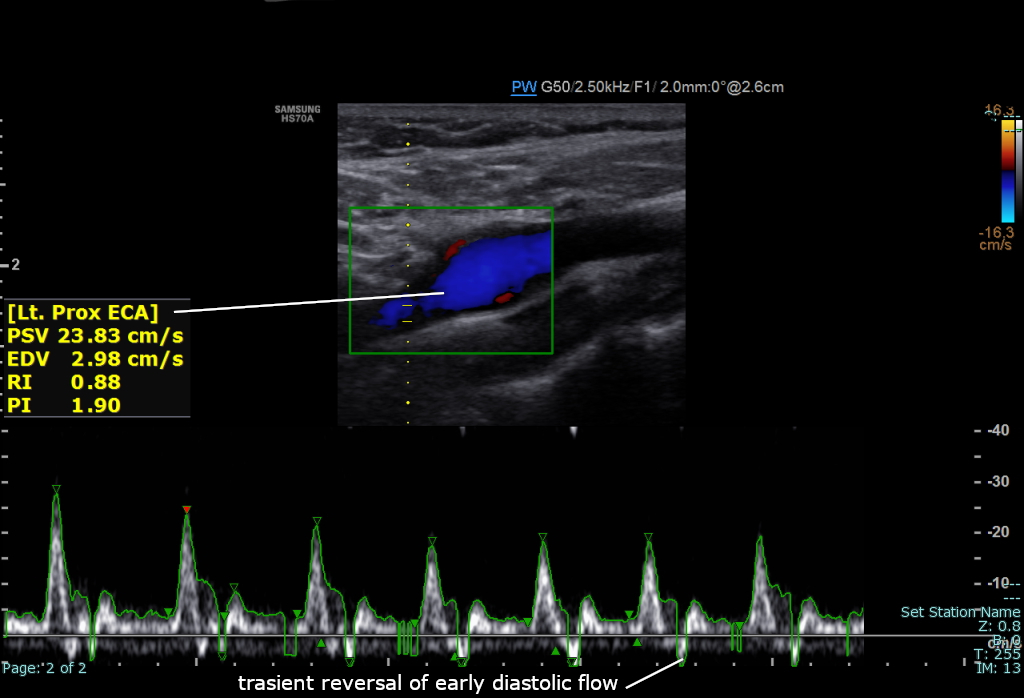

정상적인 스펙트럼 도플러 초음파를 사용한 왼쪽 바깥목동맥

바깥목동맥의 상태와 건강은 도플러 초음파, CT 혈관조영술, 위상 대비 자기 공명 영상(PC-MRI)을 사용하여 평가한다. 바깥목동맥의 혈류 속도는 최고 수축기 속도(PSV)와 이완기 말 속도(EDV)로 측정된다.[4]

PSV 값이 200cm/s를 초과하면 바깥 목동맥 협착의 50% 이상을 예측하는 것으로 간주된다.[5]